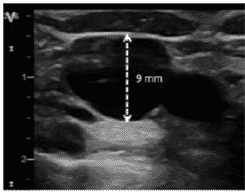

Determinar el calibre de la vena

La determinación del calibre es esencial, no solo porque aumenta la probabilidad de punción única exitosa, sino también porque el calibre determinará el tamaño del catéter.

En líneas generales, la mayoría de las guías recomiendan que el catéter no tenga un grosor mayor de 1/3 del diámetro de la vena (1 French equivale a 0.33 mm) para prevenir el riesgo de trombosis.

Para determinar el calibre se empleará el modo 2D y la función “regla”, “diámetro” o su equivalente según le modelo de ecógrafo. Una vez en este modo, el operador se dispondrá a colocar el cursor en la parte superior y medial de la pared de la vena; posteriormente trazará una línea recta hasta llegar al borde opuesto de la pared, obteniéndose, así, el diámetro antero- posterior.